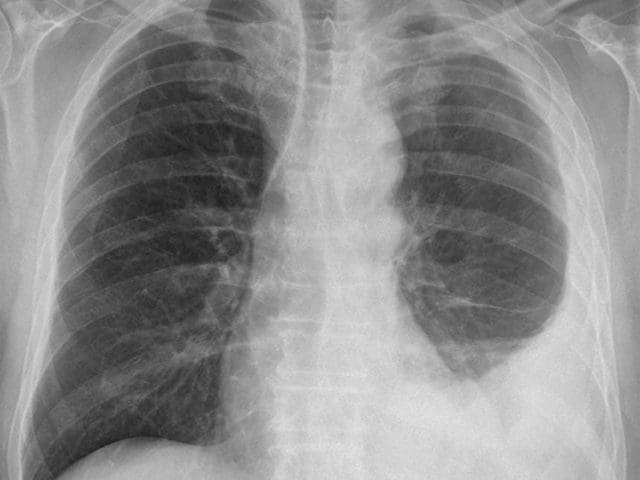

(…) Es gibt auf Grund der langen Latenzzeit noch keine Daten bezüglich dem Ausbrechen einer Berufskrankheit bzw. einer eingeschränkten Berufsfähigkeit wegen stattgefundener Asbestexpositionen seit 2008. Aus den Daten der letzten Jahrzehnte ist allerdings eine Zunahme der Berufskrankheitsfälle durch Asbest seit dem Verbot von 1990 zu verzeichnen. Die Konsequenzen sind alle Abstufungen gesundheitlicher Einschränkungen, Beeinträchtigungen der Lungenfunktion, damit verbundenes frühzeitiges Verlassen der Berufsfähigkeit bis hin zum Risiko einer letalen Erkrankung.(…)

Die seit 1997 geführte Statistik der AUVA in Sachen Asbest-Vergiftung zeigt ein mehr als deutliches Bild. So haben sich die Erkrankungen seit 1987 von damals 11 auf 2014 mit 129 mehr als verzehnfacht. Seit 2010 liegen sie regelmäßig bei einem Wert von weit über 100, die absolute Spitze wurde 2011 mit 131 Krebserkrankungsfällen erreicht.